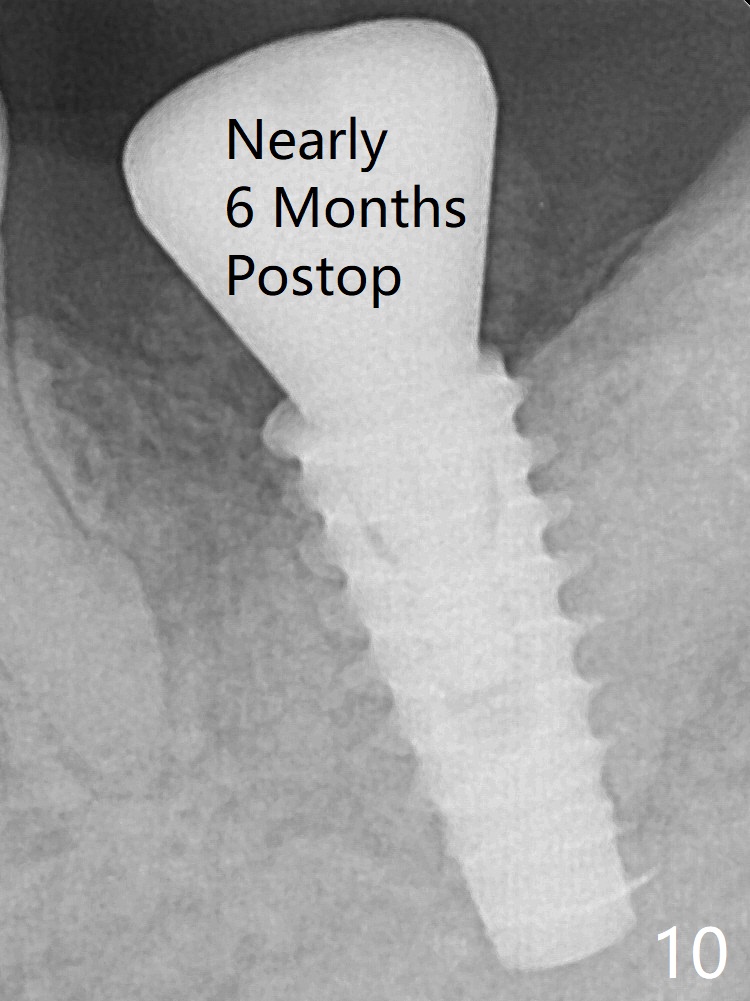

The implant is removed, cleaned with Titanium brushes and H2O2 in vitro and repositioned 12 months postop (Fig.14: arrow (gaps: post granulation tissue removal)). The gaps are regrafted with sticky bone and covered with PRF membrane and Cytoplast.取出植体,钛刷清洗,即刻植入,种深些(图十四:箭头),冠部螺纹两旁有间隙(*);放置愈合帽,最后表浅放置粘性骨粉(图十五:*)。覆盖不可吸收膜,